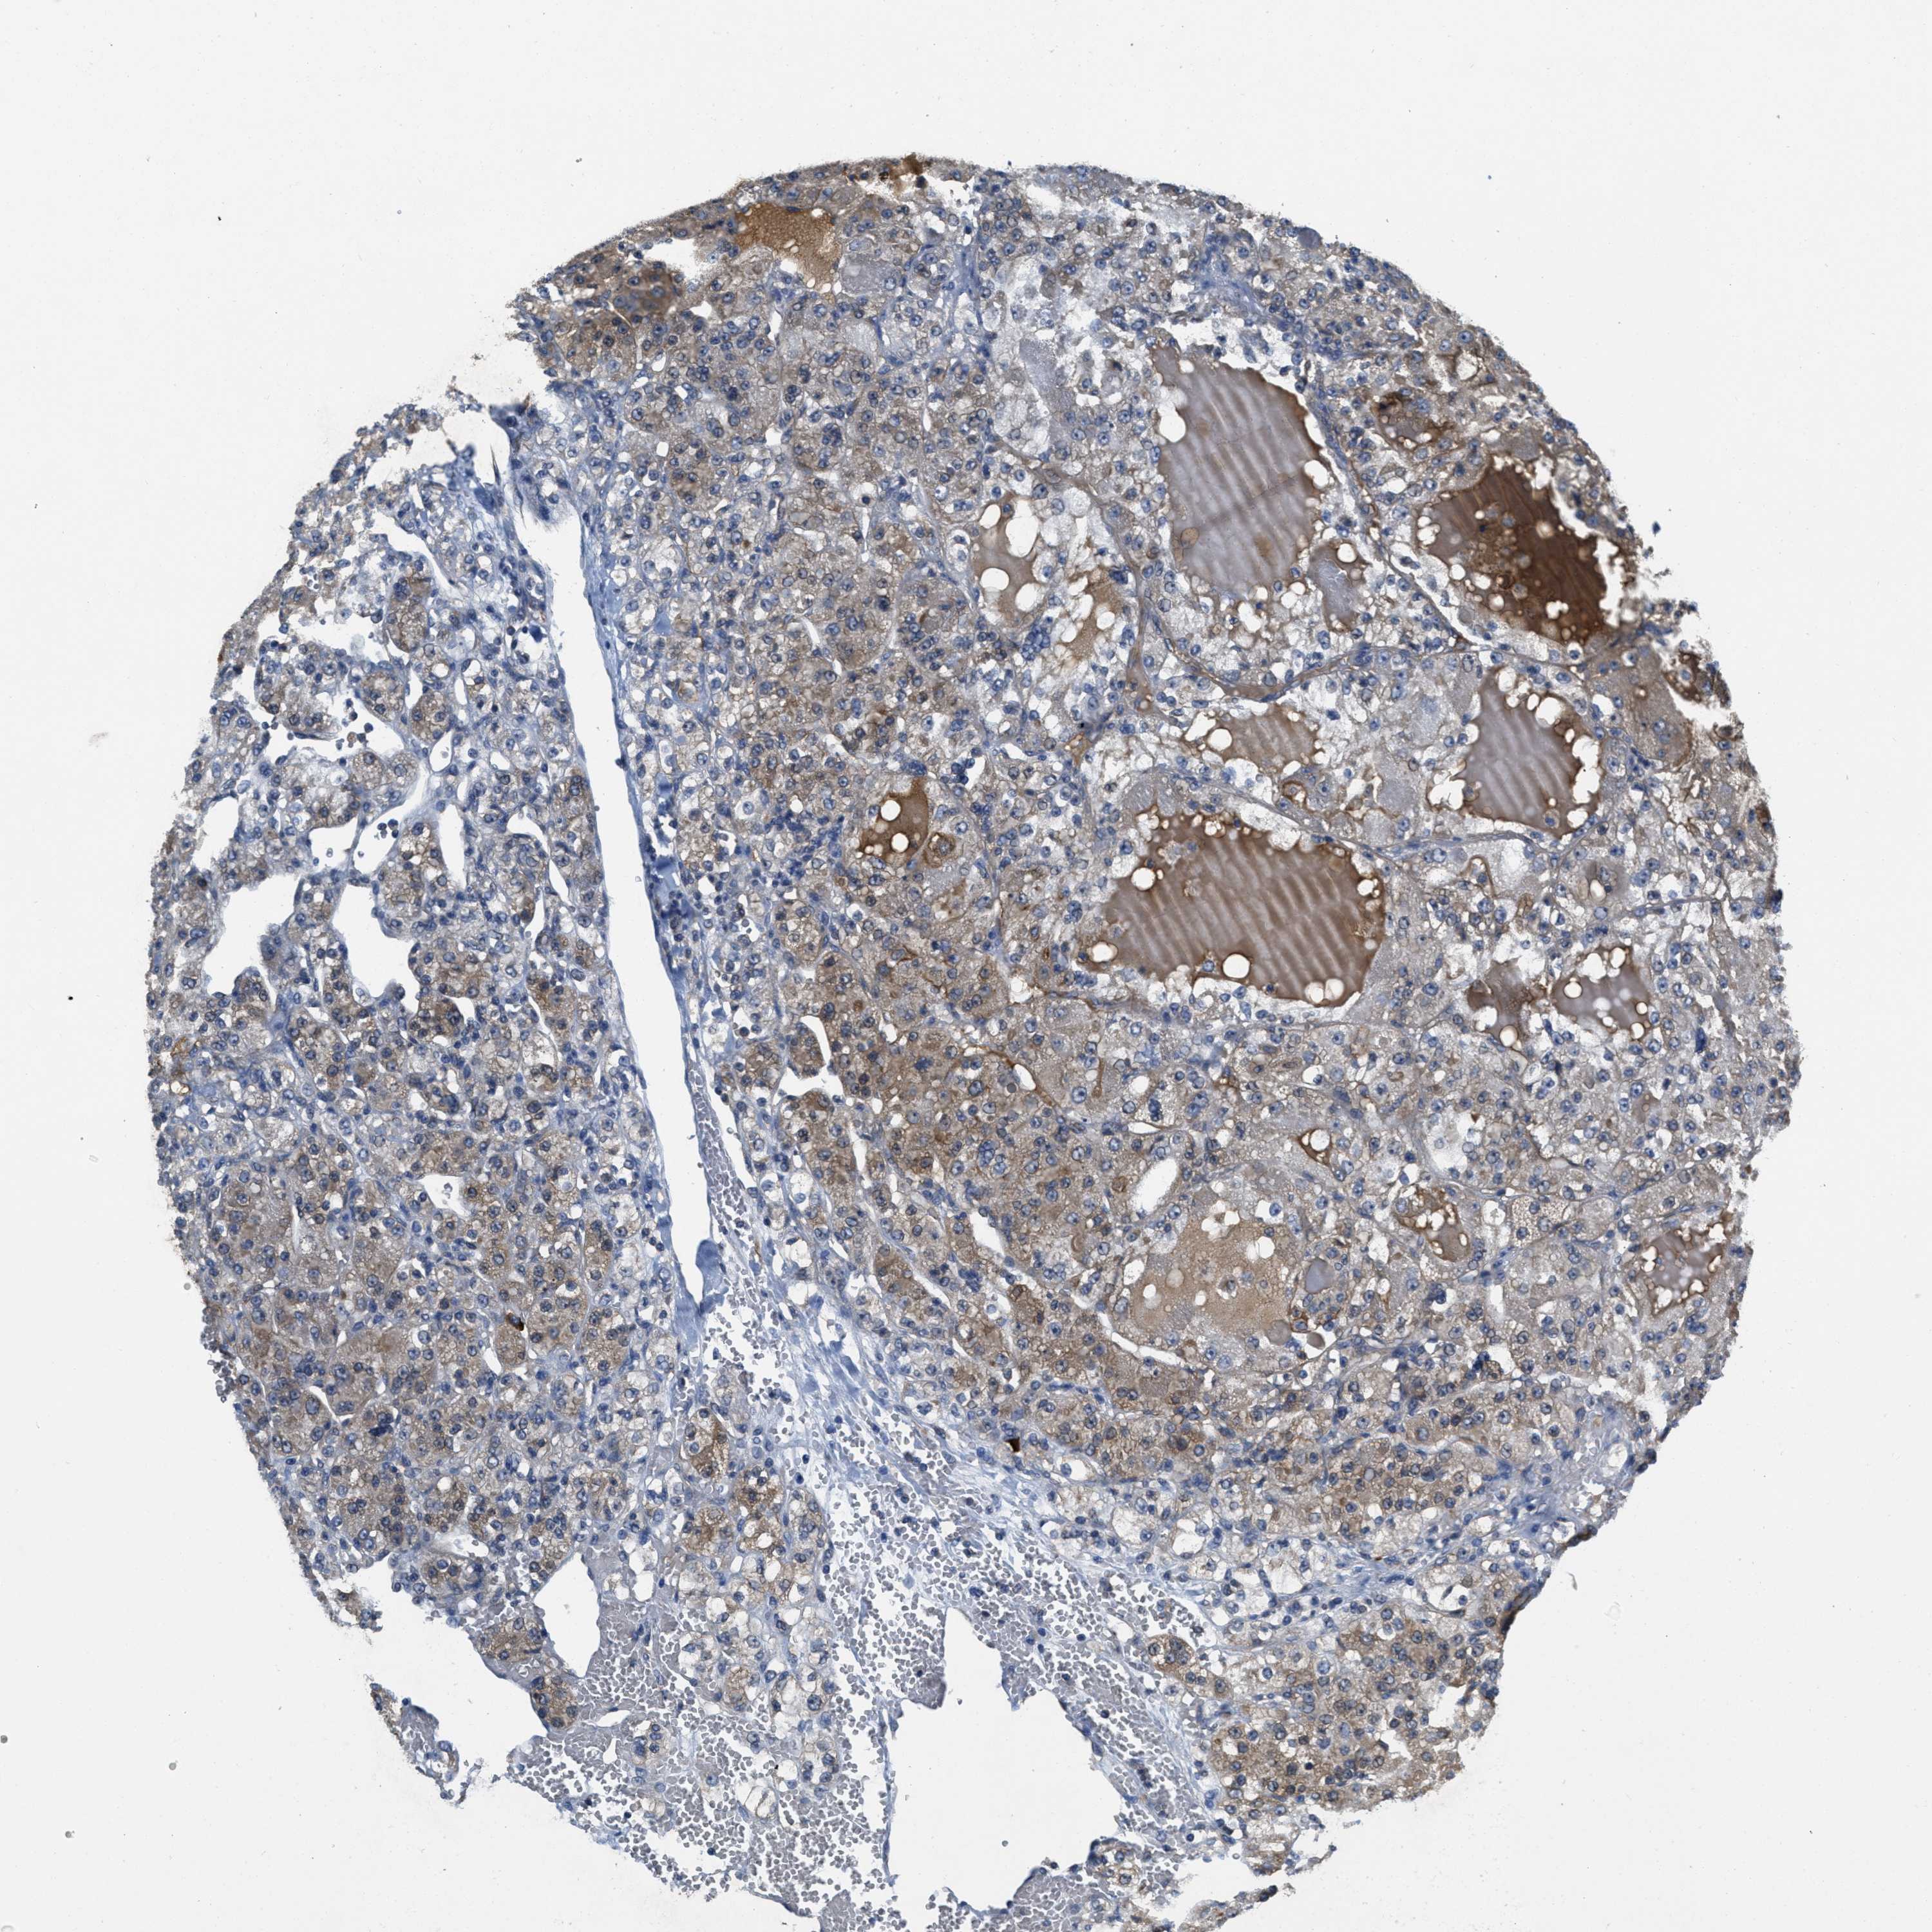

CANCER RENAL CANCER Show tissue menu

KICH TCGA KIRC TCGA KIRC VALIDATION KIRP TCGA PROTEIN RCC CPTAC PROTEIN EXPRESSION